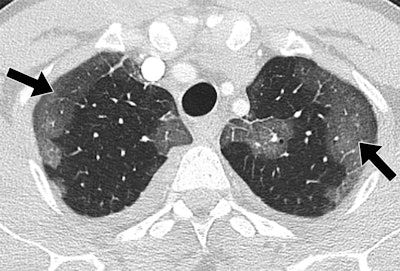

Patients hospitalized with MERS most commonly showed bilateral predominantly subpleural and basilar airspace changes, with extensive ground-glass opacities and less consolidation, concluded the study team from King Abdulaziz University Hospital in Jeddah. The subpleural and peribronchovascular nature of most of the abnormalities is suggestive of an organizing pneumonia pattern, they wrote.

The most common CT finding in hospitalized patients with MERS is bilateral predominantly subpleural and basilar airspace changes, with more extensive ground-glass opacities than consolidation, Ajlan and colleagues concluded.

"The predilection of the abnormalities to the subpleural and peribronchovascular regions is suggestive of an organizing pneumonia pattern," they wrote. "Recognizing this pattern in acutely ill patients living in or traveling from endemic areas may help in the early diagnosis of MERS-CoV infection."